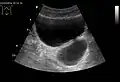

Diverticulum of the urinary bladder of a 59-year-old man, transverse plane -

Bladder diverticula as seen on ultrasound[18]